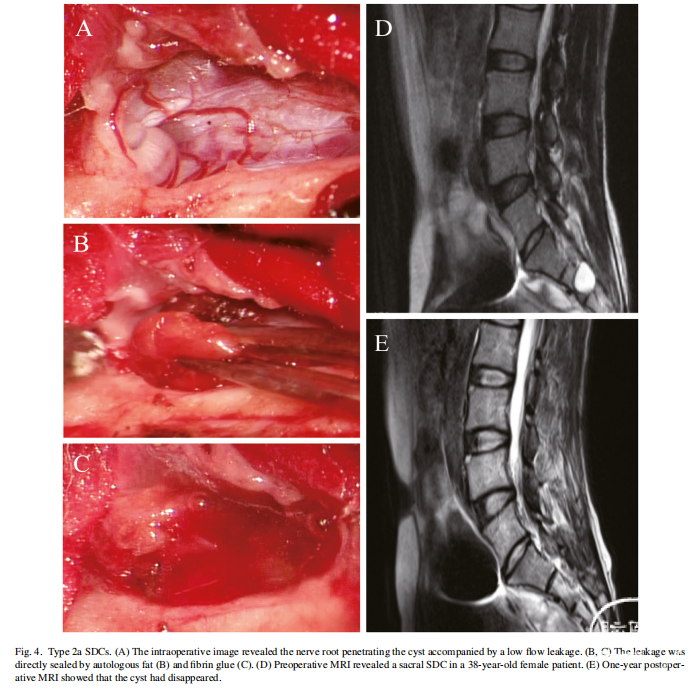

手术策略

对于不同亚型的囊肿,我们制定了相对应的手术策略。1a型SDC裂隙型漏口采用直接细线缝合,而1b型孔径型漏口采用补片或自体组织修补缝合。2a型的低流量渗漏直接用自体脂肪和纤维蛋白胶进行封堵。对于高流量的2b型,先在漏口末端缝合一针或两针,使脑脊液流量降低到类似2a型的低水平,然后用脂肪和纤维蛋白胶封堵。

2型,含有神经根的SDCs

2a型,为低流量渗漏

37例2型SDCs确诊为高流量渗漏,进行了端口缝合,随后进行了封堵(图5A-C)。36例患者症状明显改善,1例患者无明显变化。随访MR显示7例(18.92%)囊肿消失,29例(78.38%)囊肿明显缩小(图5D, E)。

对于低流量的2a型,可以用自体脂肪和纤维蛋白胶直接封堵渗漏。但2b型CSF流速较快,单纯用脂肪和纤维蛋白封堵不够牢固,可能导致术后脑脊液漏出和囊肿复发。在漏口末端进行缝合,可以有效地将高流量降低到低水平,从而提高封堵的成功率。在大多数情况下,在漏口的一端缝合一针就足够了,如果流量仍然很高,可以在另一端加缝一针。文献报道经介入治疗或开放手术,83.5%的Tarlov囊肿患者总体症状改善。本组2型SDCs经2年多的随访,症状改善率达到97.59%。我们这组病例队列中囊肿复发率和总并发症发生率与介入性或开放性手术相比都较低。尽管评价标准可能存在一些差异,我们的数据表明,显微封堵技术治疗2型SDCs取得了更好的结果。